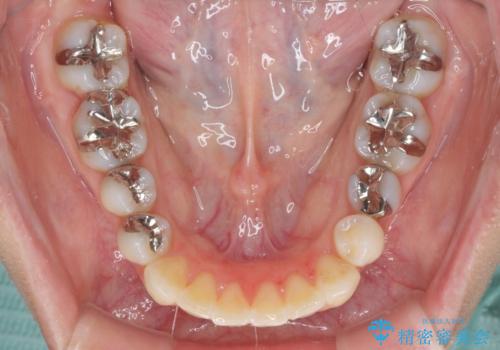

- 前歯のデコボコと矮小歯、更には痛みを感じる奥歯のむし歯を気にして来院された患者様です。

奥歯には根管治療が必要な歯があり、上顎側切歯は左右ともに矮小歯でした。

上下前歯のデコボコはワイヤーでもインビザラインでも対応可能でしたが、補綴治療が多く必要となることから、インビザラインでの矯正治療を行いながら、並行して補綴治療を行うこととしました。

まずは根管治療を行った上で矯正治療用の仮歯を装着し、矯正治療後半に補綴治療を並行して行うこととしました。